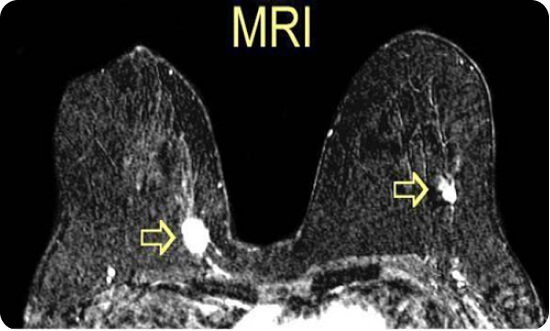

MRI Vú

- Xung 2D, 3D với độ phân giải cao

- Xung đánh giá vú có cấy siliconphần mềm tại tạo xung quanh núm vú

- MRI phổ khối u

- Đánh giá chính xác tổn thương vú với độ phân giải cao nhất